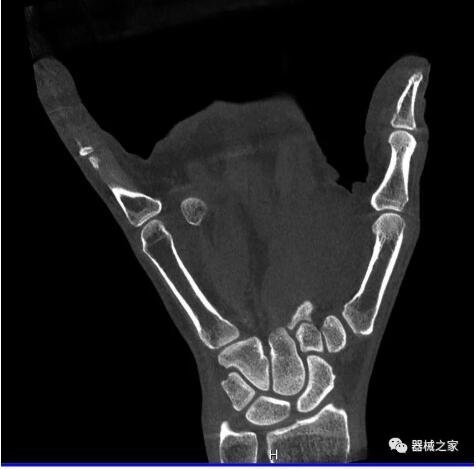

另外一款被稱為世界上最小的CT,它的重量僅300磅,不僅能夠掃查足部,還可以檢查膝蓋和上肢等。

這款CT使用非常方便,通過上下移動保持與患者的手臂或者雙腿齊平,掃描快速,僅需要30秒左右就可以完成掃查。

以上介紹的CT均來自國外同一家公司,這些CT均配置了可視化軟件,可以進行切片、3D重建以及大型CT附帶的所有典型的操作功能。

以下是這些“特立獨行”的CT所拍出來的圖像: